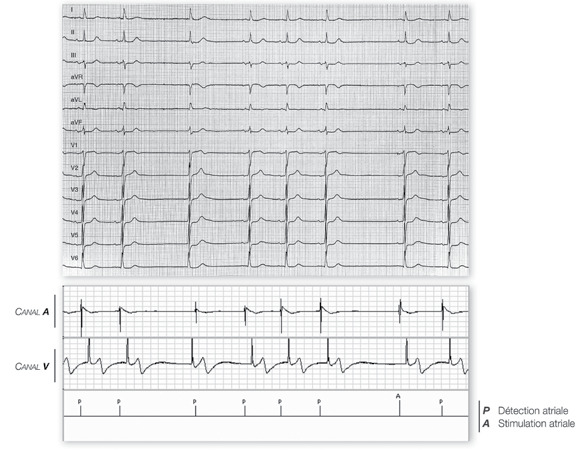

Mode AAI 30 battements/minute: initialement, activité sinusale (P) plus rapide que la fréquence minimale; première pause sinusale avec échappement jonctionnel; seconde pause avec stimulation atriale (A) après 2 secondes qui correspond à la fréquence minimale;

Un stimulateur simple chambre fonctionne en mode AAI quand une seule sonde est positionnée dans l’oreillette; le mode AAI peut également être programmé dans un stimulateur double chambre. Ces tracés permettent de mettre en évidence les caractéristiques principales de ce mode de stimulation: 1) détection et stimulation de l’oreillette, inhibition sur un événement spontané atrial; l’indication préférentielle est donc la dysfonction sinusale pure sans trouble de la conduction ventriculaire. Un stimulateur AAI permet de limiter le nombre de sondes implantées, d’assurer une fréquence physiologique au repos comme à l’effort après programmation de l’asservissement de fréquence et d’éviter toute stimulation ventriculaire inutile. 2) absence de détection ou de stimulation ventriculaire. Les stimulateurs simplechambre AAI ou la programmation du mode AAI sur un stimulateur double chambre sont formellement contre-indiqués chez les patients présentant un trouble de conduction atrio-ventriculaire permanent ou paroxystique. De même, il est préférable de ne pas utiliser le mode AAI en cas d’intervalle PR long, de trouble conductif intraventriculaire, de point de Luciani bas, de HV long. Ce mode doit également être évité chez les patients présentant une symptomatologie vagale ou un syndrome du sinus carotidien. Quand le stimulateur fonctionne en mode AAI, il peut être (valeur programmée plus basse) que pour un fonctionnement en souvent plus faible que celle des complexes ventriculaires. De même, pour éviter toute surdétection ventriculaire par la sonde atriale. baisse de la fréquence de stimulation, car chaque onde R détectée croisée (détection de l’onde R), il est possible de rendre le stimulateur pour couvrir le 2288

Une étude récente montre des résultats défavorables à l’implantation d’un stimulateur simple chambre AAI par rapport à l’implantation d’un double chambre chez les patients présentant une dysfonction sinusale. En effet, le taux de ré-intervention est plus important chez les patients implantés d’un AAI avec nécessité de rajouter une sonde ventriculaire secondairement à la survenue d’un trouble de conduction atrioventriculaire. Les indications d’implantation d’un stimulateur simple chambre AAI sont donc relativement limitées aujourd’hui. nécessaire de programmer une sensibilité plus élevée mode VVI; en effet, l’amplitude des complexes atriaux est le plus la période réfractaire peut être programmée plus longue La détection d’une onde R par un stimulateur AAI entraine une recycle l’intervalle d’échappement. En présence d’une écoute moins sensible et/ou de prolonger la période réfractaire ventricule.